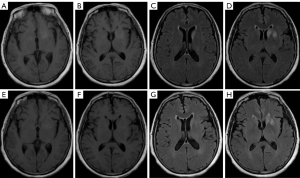

Anti-GAD65 encephalitis

All 4 patients with anti-GAD65 encephalitis were female, with an average onset age of 37±11.1 years, ranging from 26 to 52 years, with a median disease duration of 1,277 days. All patients underwent brain MRI during the acute stage, and 2 of them (50%) showed abnormalities: one patient had T2 FLAIR hyperintensity and mild DWI hyperintensity in the left cerebellopontine crus and right brachium pontine (Figure 7A-7D), the other showed bilateral hippocampal swelling with T2 FLAIR hyperintensity and mild DWI hyperintensity (Figure 7E,7F). Contrast-enhanced scanning was performed on one patient, which showed no pathological enhancement.

Both patients with abnormal MRI were re-examined with brain MRI during the convalescent period, and both revealed improvement with a reduced lesion area and decreased T2 FLAIR and DWI hyperintensity. Table 6 presents the clinical and imaging characteristics of anti-GAD65 encephalitis.

In anti-GAD65 autoimmune neurological diseases characterized by limbic encephalitis or temporal lobe epilepsy (39), the brain MRI findings depend upon the course and severity of the disease. In the acute phase, the common abnormalities are unilateral or bilateral medial temporal lobe swelling and T2 FLAIR hyperintensity, which may progress to hippocampal and frontotemporal lobe atrophy during follow-up (40).

In this study, two of four cases (50%) showed abnormal brain MRI. One showed bilateral hippocampal swelling with T2 FLAIR and DWI hyperintensity, and the clinical manifestation was temporal lobe epilepsy; the other showed T2 FLAIR hyperintensity and DWI mild hyperintensity involving the left cerebellopontine crus and right brachium pontine, and the clinical manifestation was cerebellar ataxia. These results were consistent with the previous studies (39,41,42).